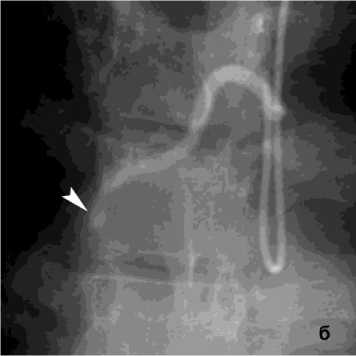

Рисунок 8. Ангиограмма правой внутренней грудной артерии (ПВГА) у пациента с ЛК 2А, клапанная эндоблокация): а – гиперваскуляризация нижней доли правого легкого; б – состояние после эмболизации ПВГА микроэмболами (710–1000 мкм ) – заполнение только ствола ПВГА

Figure 8. Angiogram of the right internal thoracic artery (RITA) in a patient with PH grade 2A (valve endobronchial occlusion): a – hypervascularization of the lower lobe of the right lung; б – status post embolization of the RITA with microembolic particles (710–1000 μm) – filling of the RITA trunk only

Рецидив ЛК после эмболизации наблюдался у 15 (10%) пациентов, в 3 случаях из них эмболизация БА была выполнена более года назад. В результате ангиографического поиска выявлены дополнительные источники ЛК: межреберные артерии – 4, внутренняя грудная артерия – 8 (рис. 8), АV – 3 (рис. 7).